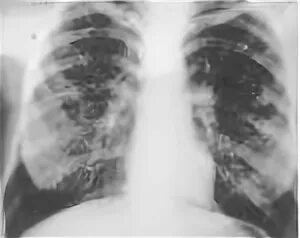

Пневмосклероз мкб 10